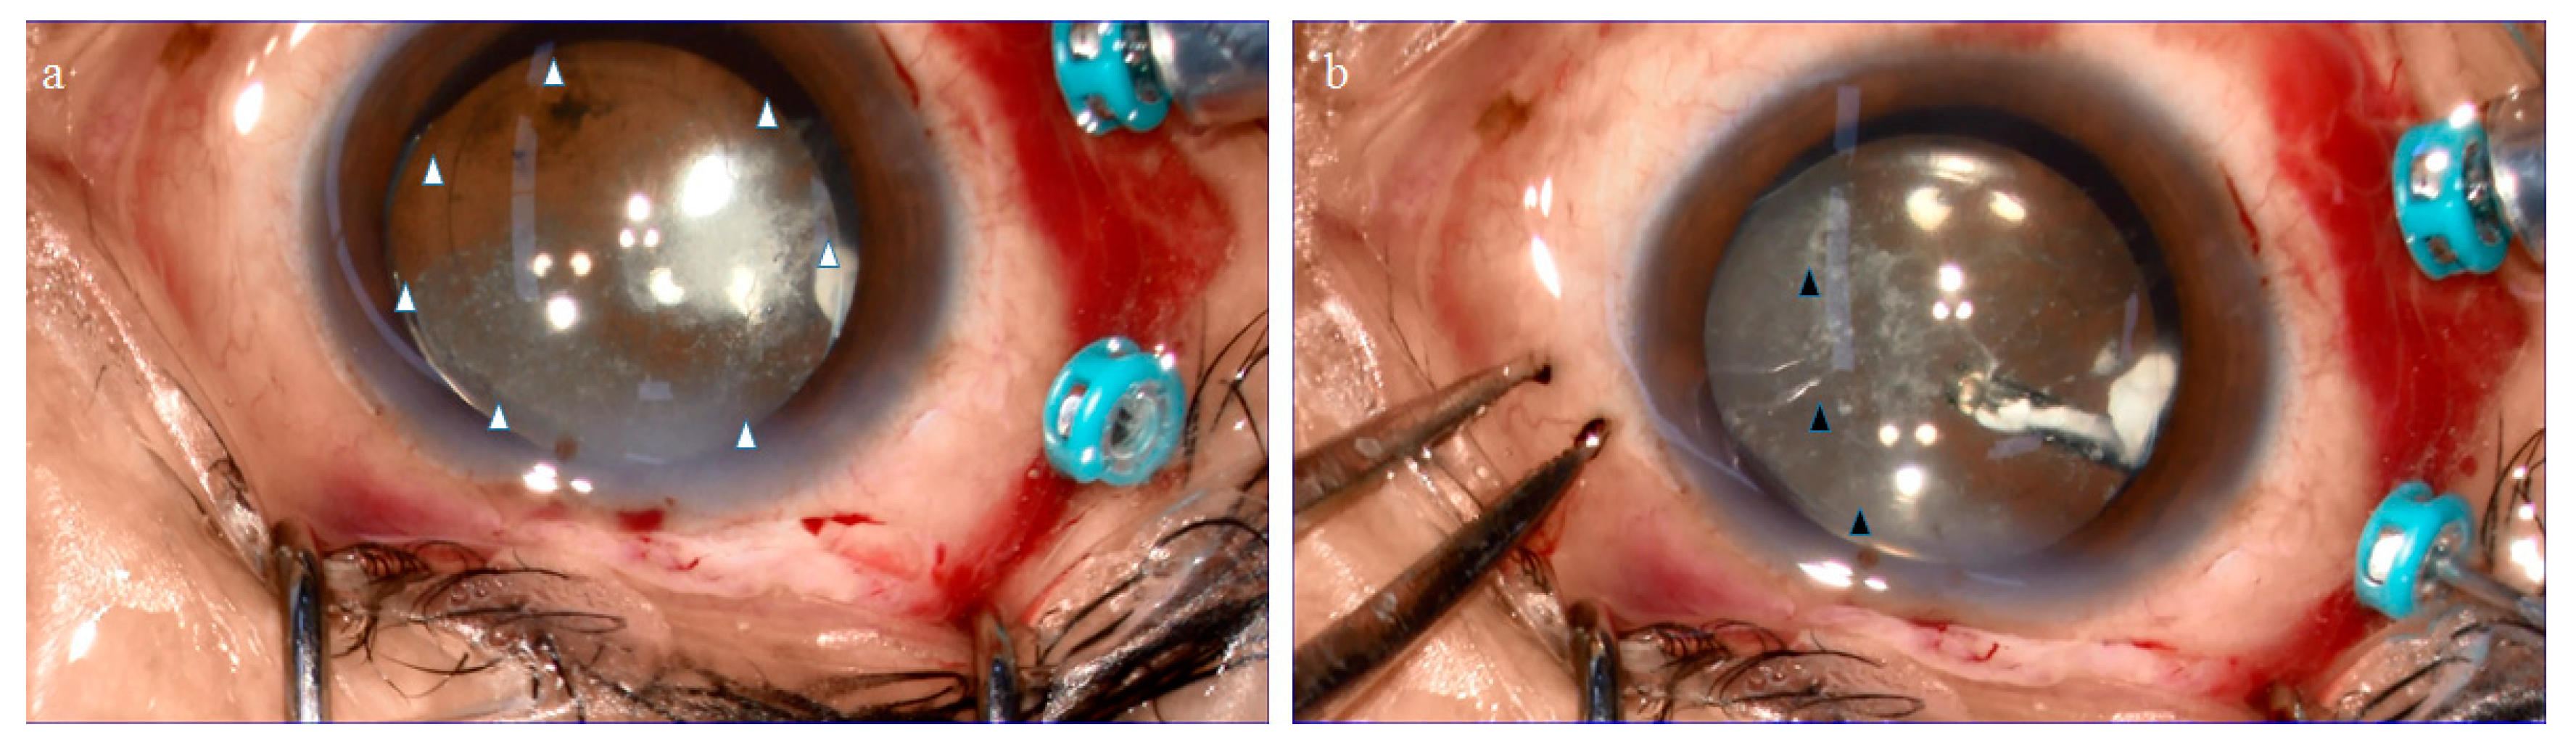

2.1. Anatomical Similarities between the BS and the BPM Observed during Specimen Collection

4.1. Collection of the BS, BPM, and VC Specimens